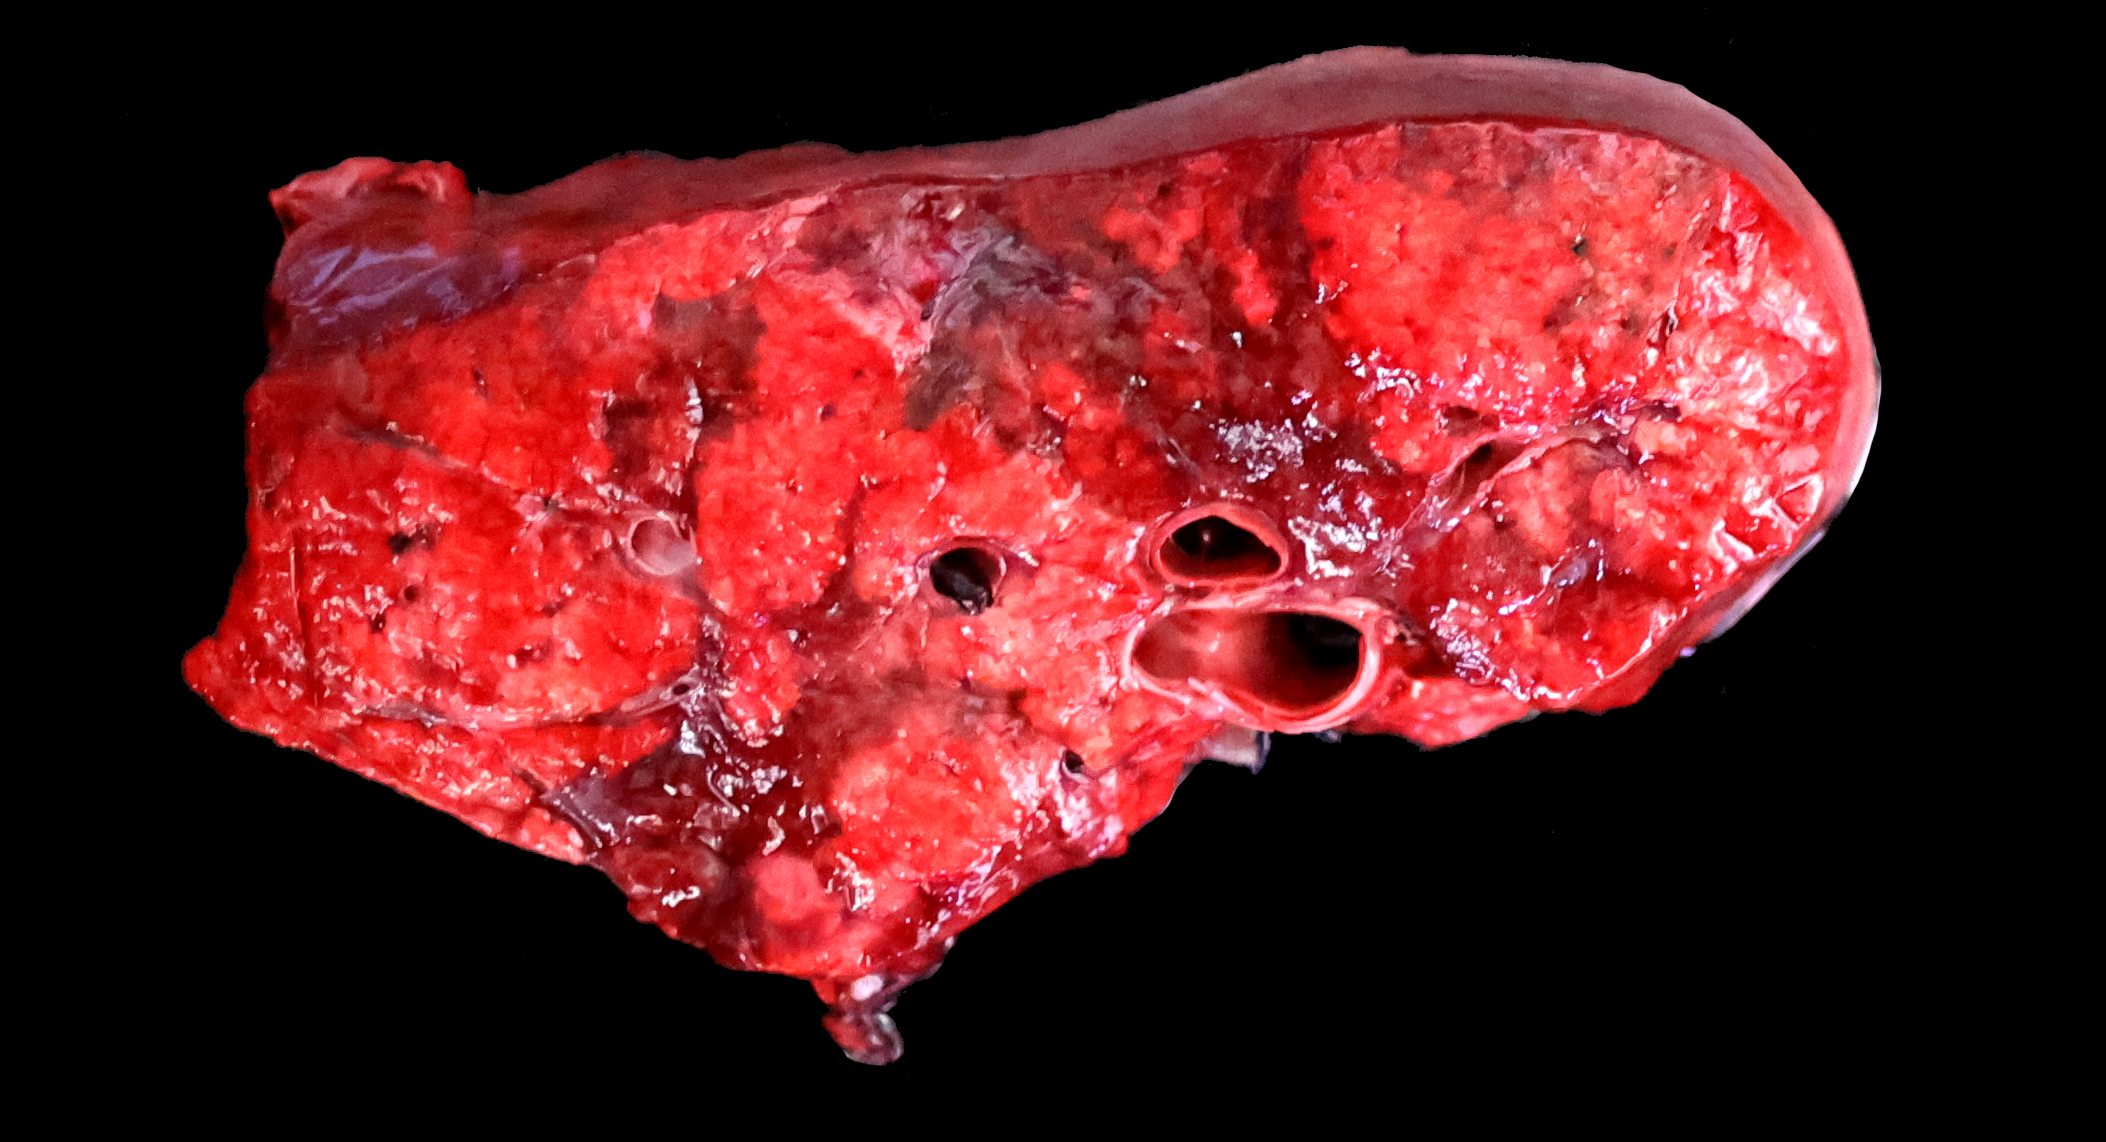

Gross Pathology:

The lungs are diffusely swollen with a lobular pattern. On the cut surface, red areas of pulmonary consolidation are seen in a lobular pattern, separated by unaffected lung lobules. Moderate amounts of thick tan exudate are noted in the airways. The trachea contains moderate amounts of stable foam. The tracheobronchial lymph nodes are enlarged.

Grossly, an influenza-infected lung has a ?checkerboard? appearance with random, alternating areas of dark red atelectasis and light pink, aerated lung. This pattern manifests because influenza does not uniformly infect every cell it comes into contact with due to varied densities of sialic acid receptors on the host cells. Dark red to purple areas of consolidation represent collapsed alveoli whose airway has been clogged by exudate and which can no longer pass air through to the alveoli.. These solidified, dark red sections contrast sharply with the lighter-colored, air-filled alveoli.